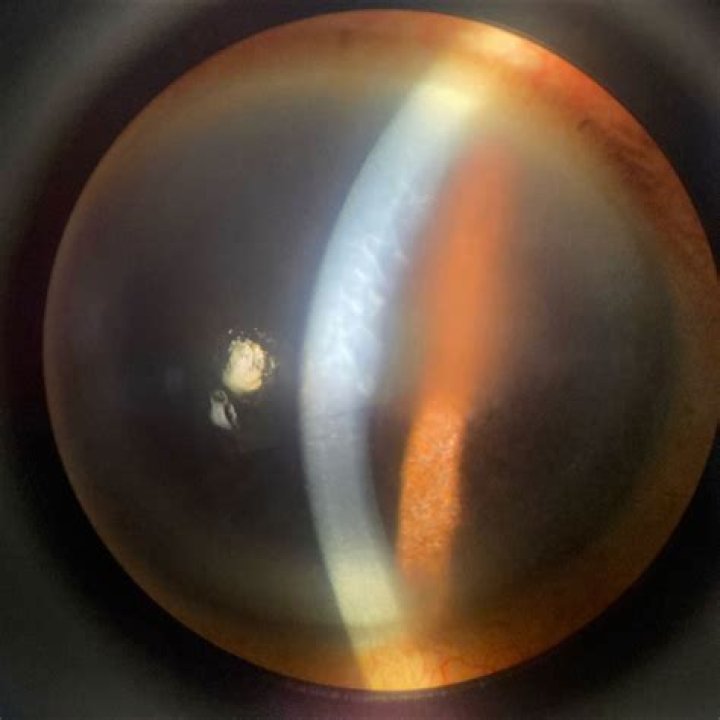

What does corneal ectasia look like?

Corneal ectasia signs and symptoms are progressive as the cornea adopts a bulging shape. The most commonly reported are: Inability to fully correct vision to 20/20 with contacts or glasses. Shadows or ghosting figures in the visual field.

“Corneal ectasia” refers to a group of non-inflammatory disorders of the eye that involve the bilateral thinning of the cornea. Keratoconus is a specific type of corneal ectasia in which the cornea thins and weakens, leading to bulging and distortion.

Corneal Ectasia Symptoms include dry eyes, blurred vision, and an increase in the symptoms of myopia. Post-LASIK can also be a cause for Corneal Ectasia symptoms like distorted vision and thinning of the cornea. Keratoconus is a progressive state of Corneal Ectasia, which can even lead to a cone-shaped cornea.